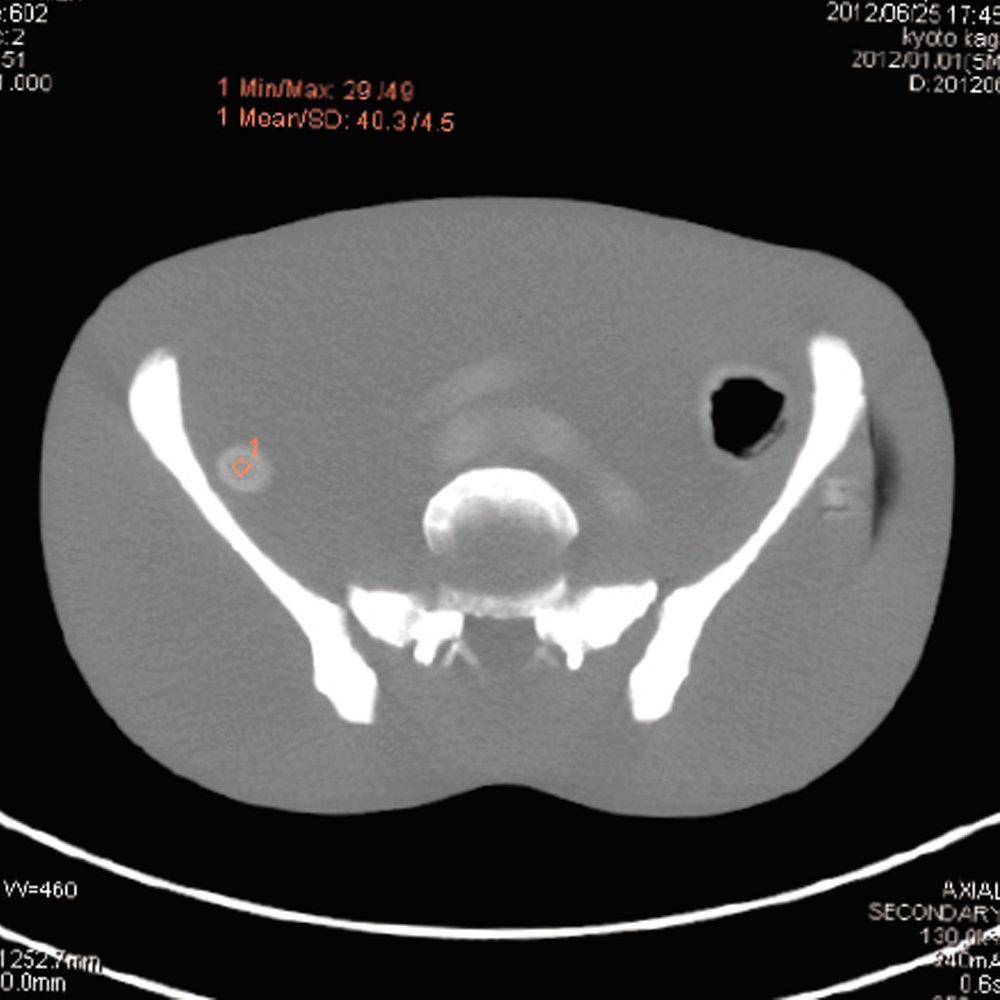

CT Whole Body Phantom - With Pathologies

1A unique, life size whole body phantom for CT provides a variety of educational application as well as visual evaluation in finding out optimal scanning conditions

| Features | 1.Radiology absorption and HU number approximate to human body 2. Main joints have close-to human articulation 3. Phantom can be disassembled into 10 individual parts |

| Training skills / Applications | Plain X-ray / CT /Basic patient positioning |

| Case / Pathology | Refer to PDF( Anatomy and Pathologies) |